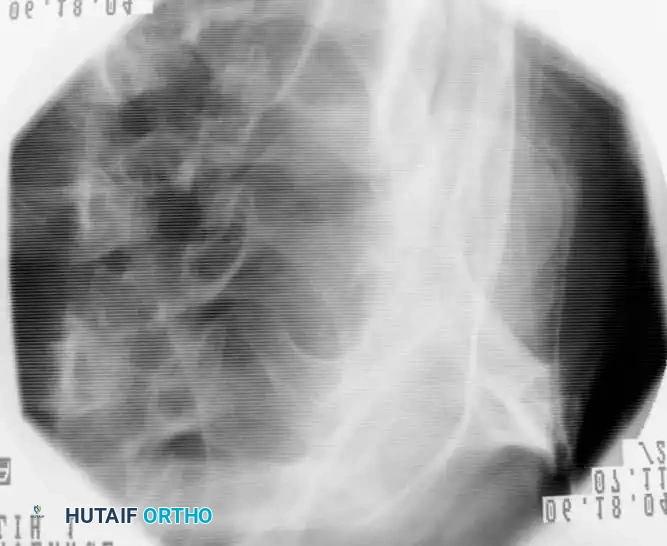

Radiographic Evaluation

A standard shoulder trauma series is mandatory for all patients suspected of a proximal humeral fracture. This series must include:

1. Anteroposterior (AP) View in the Plane of the Scapula (Grashey View): Prevents overlap of the humeral head and glenoid.

2. Lateral View of the Scapula (Y View): Assesses anterior or posterior dislocation and scapular body integrity.

3. Supine Axillary View: The most critical view for evaluating the glenohumeral joint articulation, tuberosity displacement, and articular head-splitting components.